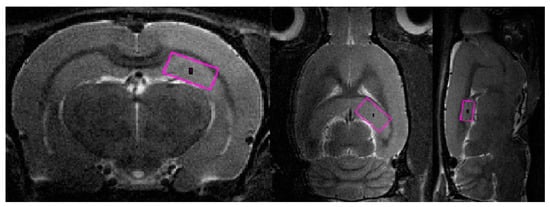

The blood supply of the brain was examined using time of flight (TOF) angiography in one scan session with MRI [56,57]. Images of the common carotid arteries (left and right; Figure 14) were obtained in a two-dimensional projection (an example is shown in Figure 15), which, by means of the ParaVision5.1 MIP (maximum intensity projection) option, were converted into 3D images. The measurement of the size of the vessels was performed using an ROI placed 2 mm proximal to the bifurcations of the carotid arteries, which were determined from 3D images. Along with the imaging of angioarchitectonics, the blood flow velocity was assessed by the method of phase contrast angiography PCA (phase contrast angiography). The measurement was performed in a single cross-sectional main blood flow section, also guided by a 3D model (an example of PCA phase contrast angiography is shown in Figure 2). We performed these measurements 2 mm proximal to the bifurcations of the carotid arteries, that is, in full accordance with the area of measurement of dimensions of the vessels’ lumen. Additionally, the maximum blood flow velocity in the central part of the artery and the average linear blood flow velocity for the entire section of the lumen of the artery were determined. Volumetric blood flow (mL/min) was calculated based on the mean blood flow velocity and cross-section. All hemodynamic characteristics were obtained in a 2 min recording interval with averaged values as a result of several complete heartbeat cycles. The following indicators were used in the paper: the speed of blood flow in the left and right common carotid arteries (velocity of OSA L, cm/s; velocity of OSA P, cm/s); the area of the lumen of the left and right common carotid arteries (lumen o.s.a. L, mm2; lumen o.s.a. P, mm2); volumetric blood flow of the left/right common carotid artery and their sum score (o.s.a. blood flow L, mL/min; o.s.a. P blood flow, mL/min; o.s.a. blood flow, mL/min).

Figure 14. The images of the carotid arteries in three projections (in order to select the area of blood flow assessment).

Figure 15. (Left) 2D TOF image of carotid arteries; (right) 2D image of the same area obtained using PCA.